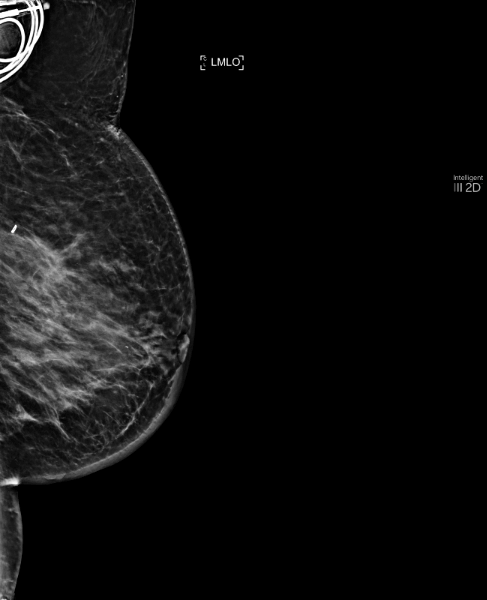

Pendant une mammographie de suivi après tumorectomie du sein gauche. Le radiologue ne retient pas d’anomalie suspecte à la première lecture.

MammoScreen l’informe d’une anomalie scorée 6 et 5 externe droite sur les coupes de tomosynthèse. La relecture de la tomosynthèse orientée par MammoScreen lui permet de retenir une petite masse suspecte.

Les examens complémentaires ont mis en évidence un petit cancer infiltrant.